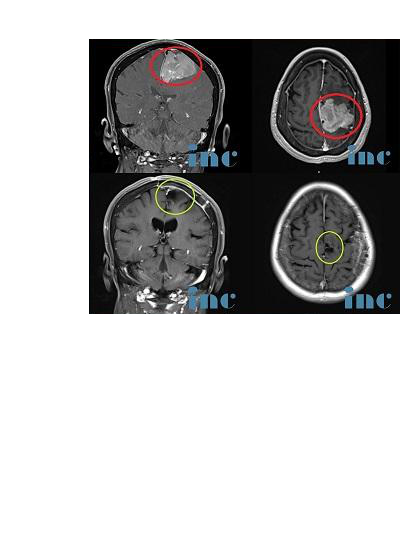

病史:王女士,60+岁,退休老师,2012年就检查出有“左侧额部大脑镰旁脑膜瘤”,由于肿瘤不到3cm加上无症状,前沿行了保守治疗。2018年复查,脑膜瘤已大于5cm,逐渐出现肢体无力,复查MR显示肿瘤侵犯静脉窦、压迫功能区。国内各大医院求诊,均被告知手术难度大,肿瘤因为靠近大静脉窦难以全切,且肿瘤靠近运动功能区,术后瘫痪可能较大(60-全切不等),而这对于人和一个人和家庭都是惨痛的,除了生活难以自理的经济负担,对于病人和家人也是较大心理负担。

德国INI巴特朗菲教授手术情况:肿瘤全切、矢状窦成功重建、运动功能区无损伤。术后当天即拔插管,术后1天迁出ICU,术后2天,可以在护理人员搀扶下走路康复训练,术后5天已经可以独自走路,无需陪同,肢体肌力明显好转,术后1周+,恢复地和正常人一样,精神状态很好。